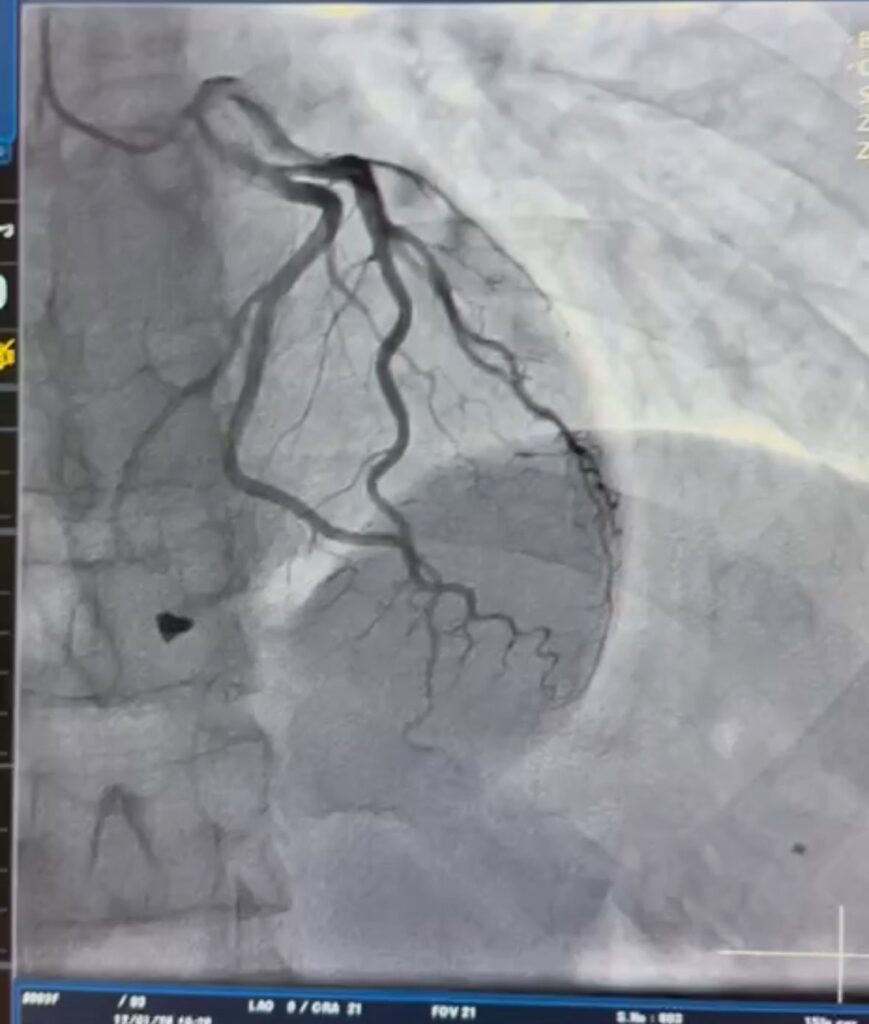

Ретельне обстеження пацієнта показало, що металевий уламок «застряг» у зоні клапанного апарату серця, а також пошкодив папілярний мʼяз тристулкового клапана. Тож травма загрожувала роботі клапана серця.

«Після детального аналізу анатомії травми кардіохірургічною командою лікарні виконано видалення вогнепального осколка та пластику тристулкового клапана, що дозволило відновити його функцію і забезпечити стабільну роботу серця», – йдеться у повідомленні закладу.